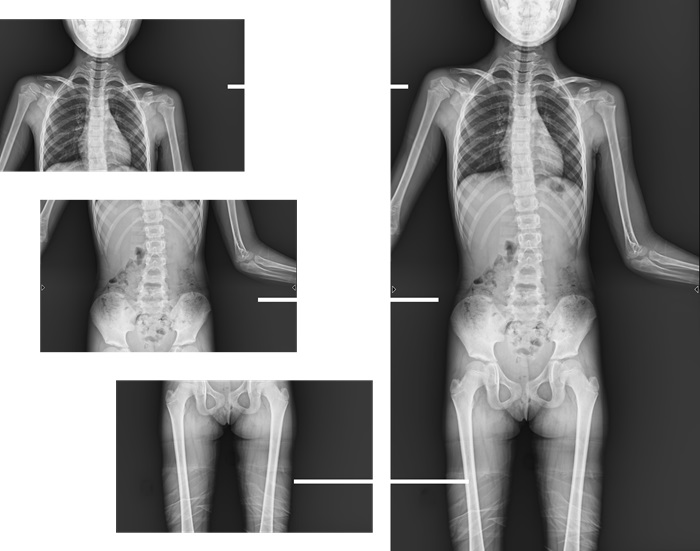

而且,影像采集幅面大,17×17英寸超大視野可覆蓋成年人的全胸全腹,并且能在連續(xù)動(dòng)態(tài)中實(shí)時(shí)高清點(diǎn)片,從而達(dá)到精準(zhǔn)診斷的目的。設(shè)備靈活高效的多維度運(yùn)動(dòng)設(shè)計(jì),也帶來了更加智能化、人性化操作體驗(yàn),可大幅提升檢查效率。

與此同時(shí),普利德動(dòng)態(tài)平板DRF還具有全身拼接功能,尤其適用于全脊柱和全下肢攝影,為臨床提供高精度圖像,輔助脊柱畸形矯形治療、康復(fù)檢查。